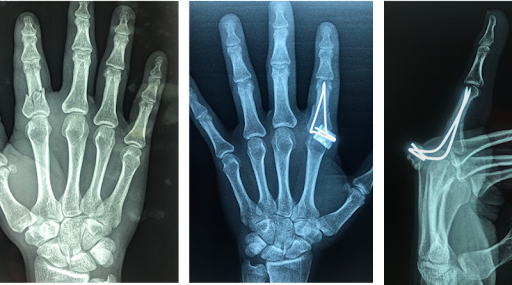

• My first broken bone

I broke a bone falling in a mcdonalds at mcdonalds attractions